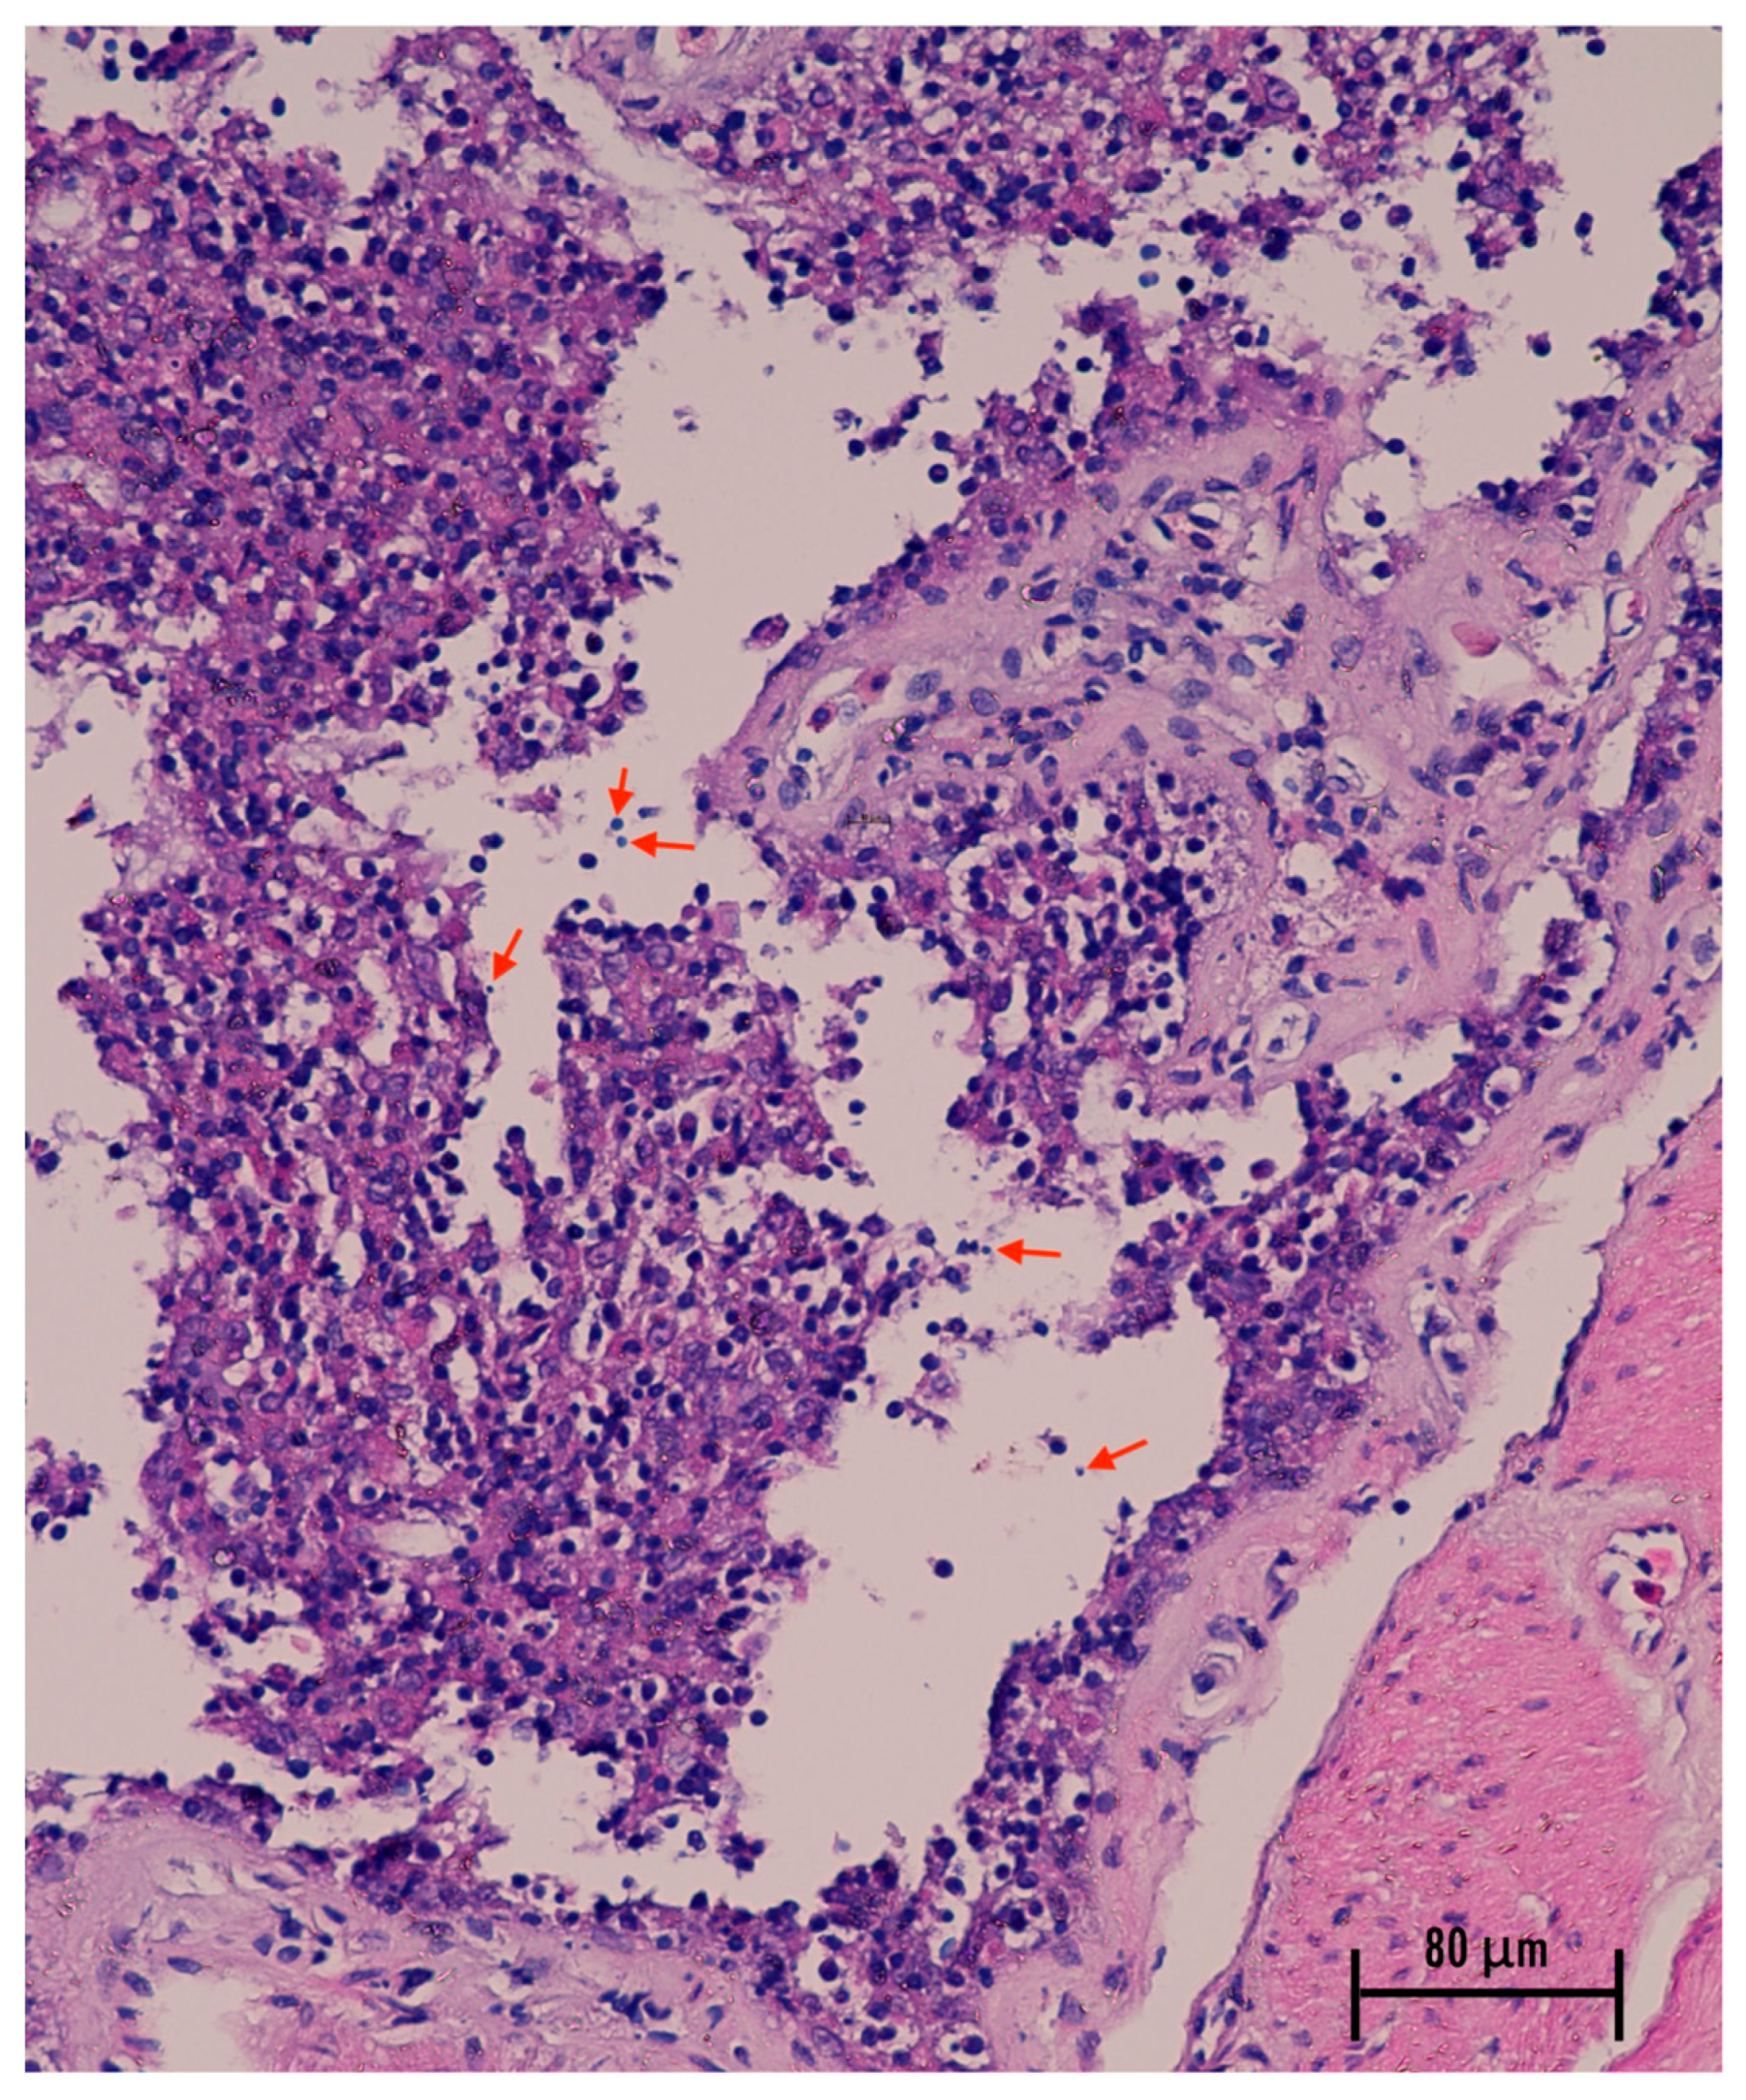

3.3. Gross and Histopathological Findings in Deceased Leopard Geckos